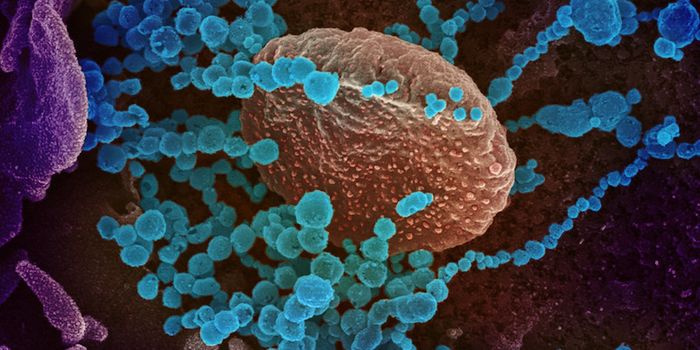

SEP 07, 2021MicrobiologyThe world has rapidly become familiar with sarbecoviruses, two of which jumped to humans in recent years. The first was ...

DEC 24, 2020MicrobiologyThe UK recently reported that it had detected a new variant of the SARS-CoV-2 pandemic virus, which causes COVID-19. Thi ...